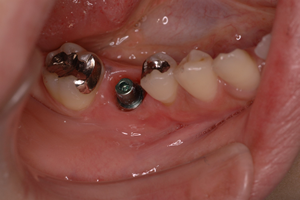

4.<インプラント1次手術>

骨の中にインプラント本体を植え、歯茎を閉じます。インプラントを植えること自体はさほど時間はかかりませんが、手術前にお口の中の清掃をしたり、レントゲンでインプラントを確認をしたり、手術後の全身状態の経過を診ますので、当日は十分な時間の余裕をみておいてください。

インプラントが骨と結合するのに3ヶ月ほど待ちます。

5.<インプラント2次手術>

インプラントが骨と結合した後、歯茎を貫通したふたを取り付けます。1回法の手術では最初の手術でそこまでしますので、2次手術は必要ありません。

歯茎の形態が落ち着くまで、1ヶ月ほど待ちます。

6.<仮歯の装着>

二次手術後の歯茎の治りを待って、仮歯を作製し、インプラントに負荷をかけていきます。それと同時に実際に使用してもらいながら、噛み合わせ、清掃性を調整します。

状態によって異なりますが、1~3ヶ月ほど経過を診ていきます。